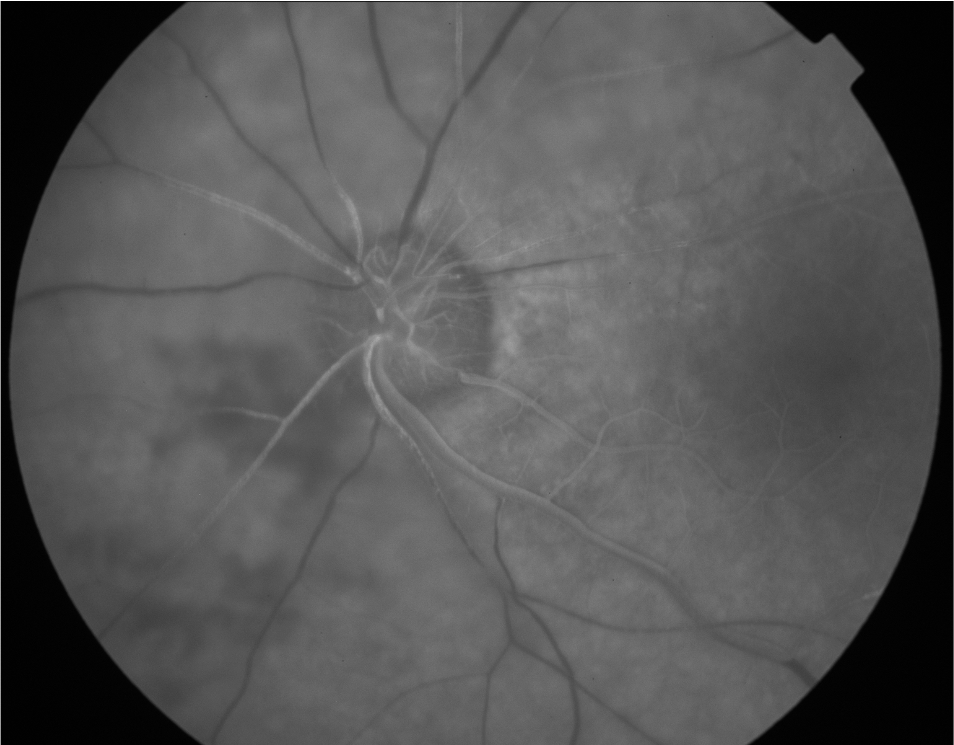

• Blocked Fluorescence Due to Vitreous Hemorrhage

Reduced visibility of underlying retinal or choroidal circulation due to a barrier located anterior to that circulation.

• Vitreous material